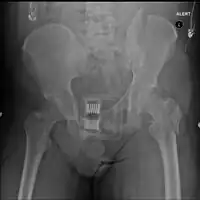

Initial

A high index of suspicion should be held for pelvic injuries in any one with major trauma. The pelvis should be stabilized with a pelvic binder.[13] This can be a purpose made device; however, improvised pelvic binders have also been used around to good effect.[14] Stabilisation of the pelvic ring reduces blood loss from the pelvic vessels and reduced the risk of death.

Surgery

Surgery is often required for pelvic fractures. Many methods of pelvic stabilization are used including external fixation or internal fixation and traction.[15][16] There are often other injuries associated with a pelvic fracture so the type of surgery involved must be thoroughly planned.[17]